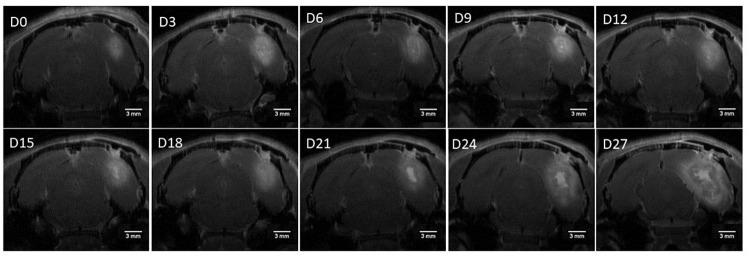

Glioblastoma (GB) is the most common and malignant primary brain tumor in adults with a median survival of 12-15 months. The F98 Fischer rat model is one of the most frequently used animal models for GB studies. However, suboptimal inoculation leads to extra-axial and extracranial tumor formations, affecting its translational value. We aim to improve the F98 rat model by incorporating MRI-guided (hypo)fractionated radiotherapy (3 x 9 Gy) and concomitant temozolomide chemotherapy, mimicking the current standard of care. To minimize undesired tumor growth, we reduced the number of inoculated cells (starting from 20 000 to 500 F98 cells), slowed the withdrawal of the syringe post-inoculation, and irradiated the inoculation track separately. Our results reveal that reducing the number of F98 GB cells correlates with a diminished risk of extra-axial and extracranial tumor growth. However, this introduces higher variability in days until GB confirmation and uniformity in GB growth. To strike a balance, the model inoculated with 5000 F98 cells displayed the best results and was chosen as the most favorable. In conclusion, our improved model offers enhanced translational potential, paving the way for more accurate and reliable assessments of novel adjuvant therapeutic approaches for GB.